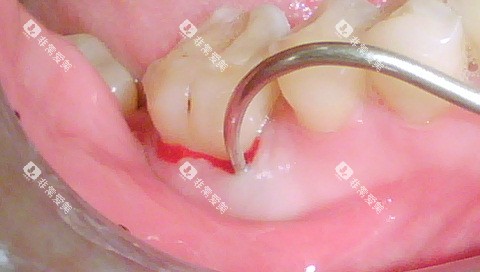

对于常见的口腔疾病,如龋齿填充、牙周炎治疗、根管治疗等,长治第二人民医院口腔科的收费都处于较为合理的水平。

在长治第二人民医院口腔科,很多常见的口腔治疗项目都在报销范围内,如拔牙、补牙、根管治疗等。